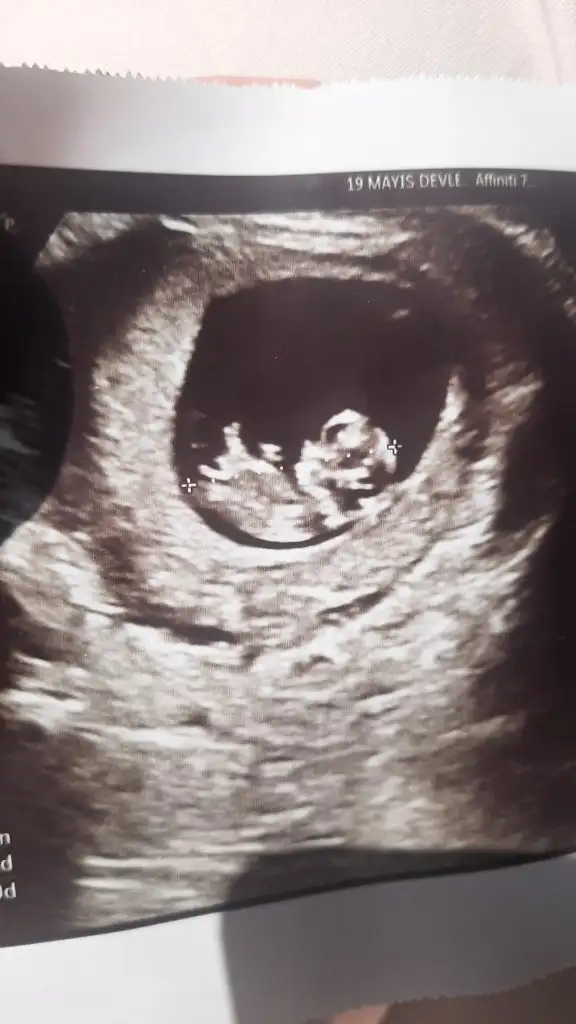

Bana da bakar mısın lütfenBi daha ne zaman gidersen nubu görülebilir belki düzgün doktorun tahmin yapmazsa atabilirsin söylerim ben daha önce de ilgim vardı bakıyordum eşe dosta

kaç haftalık burdaaBana da bakar mısın lütfen

Ay hem erkeğe hem kıza benziyor bebeğin duruşu çok yanıltıcı yorum yapmak doğru olmazz bi daha gidersen yada başka ultrason varsa atarsan bakayımBana da bakar mısın lütfen

Banada erkek gibi,Kizlar benim bebisiminde cinsiyet tahimininde bulunurmusunuz? Karindan cekildi 11+5